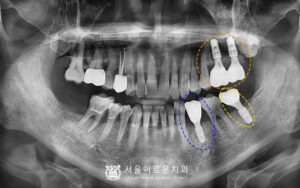

본.원에 처음 오셨던 60대 남성분의 사진입니다.

왼쪽 위에 큰 어금니를 보시면 과거 타원에서 신경치료를 했으나

뿌리 끝에 염증이 생긴 것을 알 수 있었습니다.

바로 옆에 위치한 어금니도 상태가 좋지 않았는데요.

치주염이 많이 진행되어

치아가 심하게 흔들리는 상태였습니다.

또한, 아래 양쪽 큰 어금니가 1개씩 상실된 상태였습니다.

4개의 치아를 발치한 뒤,

뼈이식을 동반한 임플란트를 바로 식립하여

촬영한 x-ray 사진입니다.

기존에 상실되어 없었던

왼쪽 아래 큰 어금니 부위에도

임플란트를 추가로 식립하였습니다. ^^

환.자분의 경우 치주염이 많이 진행된

상태로 잇몸뼈가 상당수 흡수되어

골이식을 동반하였는데요.